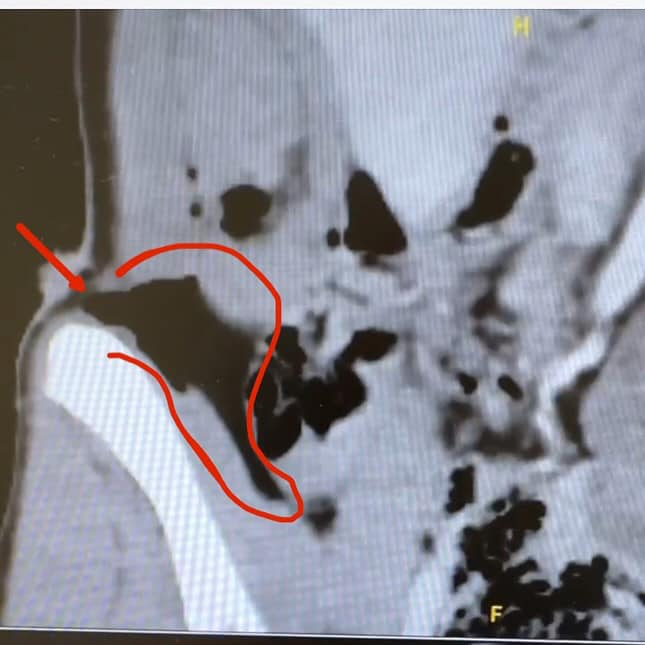

There’s been a lot of speculation about what caused the puncture wound…and a lot of discussion around the “clean hill initiative”. Some are saying the b-net pin, some are saying the base of the gate, some are speculating about the backpack next to the b-net. Of course, I am fully in support of more safety measures on hill. But, I think in my case, the damage was done before I got close to the net…and in addition to my own coaches and the volunteers who helped me, I want to thank Jojo (coach for Switzerland) who was first to get to me and helped soo so much. After reviewing the video several times, we think it was the tip of my ski pole…given the size and shape of the point of entry. Maybe it pierced in, and then I rolled over it which is what dug out the small cavern… hard to say, really. We’re just glad it’s limited to muscle damage.